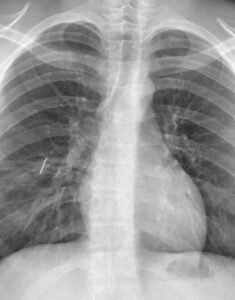

Un equipo médico del Hospital Interzonal San Juan Bautista logró extraer con éxito una aguja alojada en el pulmón de un joven derivado desde Tinogasta.

Tras un trauma penetrante de tórax, el paciente fue sometido a una cirugía abierta de una hora y media, ya que la ubicación del objeto impedía la expansión pulmonar.